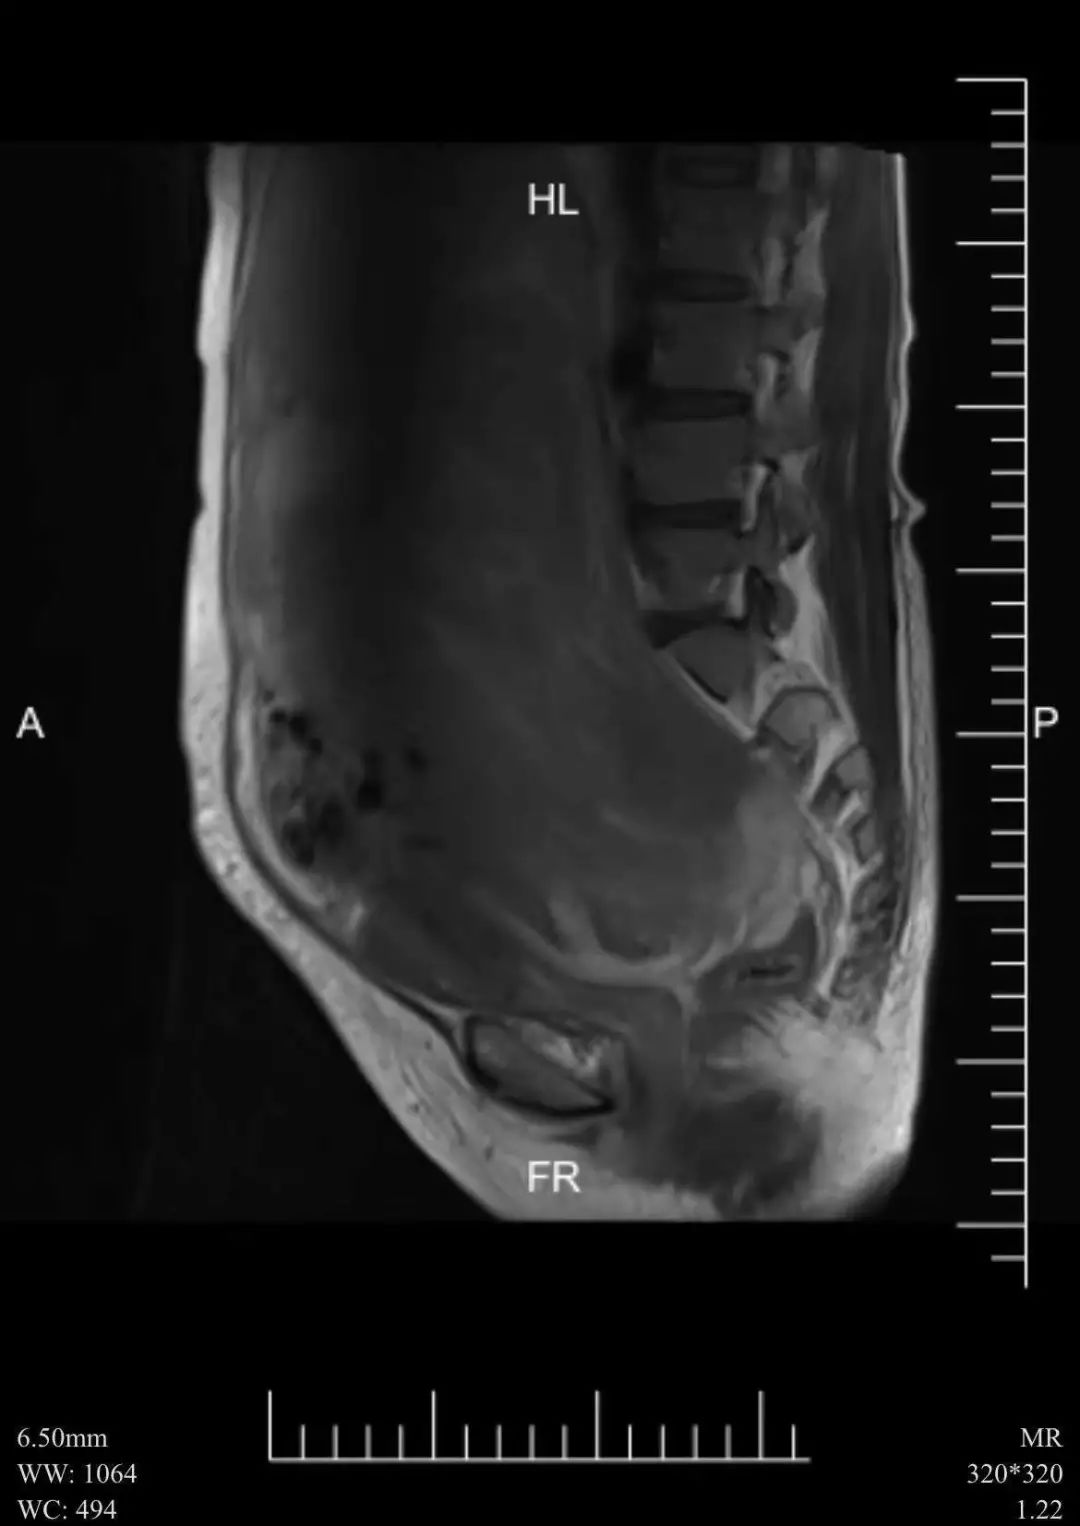

四十余岁女士,腹部似足月怀胎,难道是高龄产妇怀上第三胎?一场手术“减肥”十斤,背后故事令人唏嘘……

本帖最后由 拽老猫 于 2022-3-17 08:58 编辑 年龄46岁有余的王女士,身似足月怀胎,难道是高龄产妇怀上三胎?一场手术,数个小时,女士竟瘦身十余斤?这些咄咄怪事究竟原因如何—不幸!身患多重疾病患者王女士, ...